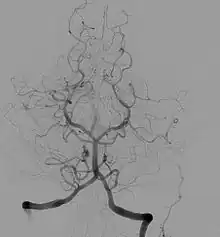

Angiographie cérébrale

Elle est l’application de la méthode de l’angiographie au niveau cérébral. Elle est utilisée en diagnostique et en interventionnelle. Les principales pathologies sont des dilatations des vaisseaux (anévrismes), le rétrécissement de vaisseaux (sténose) ou le blocage.

Elle est utilisée pour diagnostiquer des anomalies sur les vaisseaux sanguins du cerveau ou menant au cerveau (carotides). Ces différentes pathologies vasculaires peuvent être : un blocage (thrombose) ou un rétrécissement (sténose) d’un vaisseau, un anévrisme, une malformation artério-veineuse. On peut réaliser cet examen en préopératoire afin d’observer le système d’irrigation du cerveau. L’angiographie cérébrale permet également de diagnostiquer des pathologies non directement liées au système vasculaire mais ayant une influence sur celui-ci. Elle permet de visualiser des tumeurs, des œdèmes, des hernies, des vasospasmes, l’augmentation de la pression intracrânienne et l’hydrocéphalie.

L’apparition de nouvelles techniques d’imagerie non invasives a réduit l’importance de l’utilisation de l’angiographie cérébrale. On peut citer l’angioscanner, l’échographie doppler, l’angio-imagerie par résonance magnétique. Mais l’angiographie peut être recommandée après un examen précédent, afin d’apporter des informations complémentaires qui ne sont pas visibles par les nouvelles technologies. L’angiographie cérébrale reste l’examen le plus précis dans l’étude de la morphologie des vaisseaux sanguins, ainsi que pour fournir des données dynamiques sur la circulation.